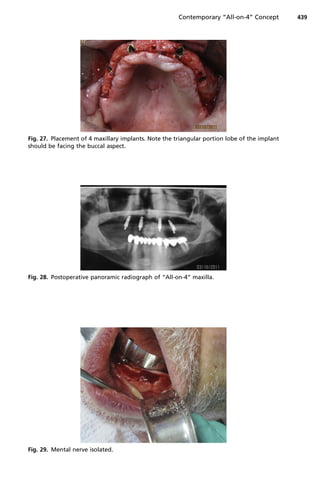

load protocol requires implant stabilization at 35 to 45 Ncm (Fig. 28).

created with attention to locate and avoid damaging the mental nerve (Fig. 29).13

Fig. 28. Postoperative panoramic radiograph of “All-on-4” maxilla.

Fig. 29. Mental nerve isolated.

Fig. 27. Placement of 4 maxillary implants. Note the triangular portion lobe of the implant

should be facing the buccal aspect.